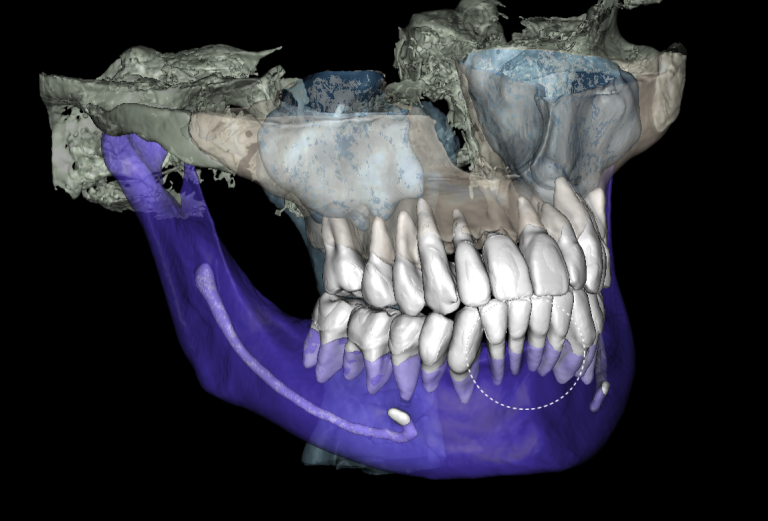

Task: Plan the implant treatment for the replacement of teeth 16 (Universal 3) and 17 (Universal 2), reduce the time required for surgical template fabrication, and improve the accuracy of its fit. Using the “STL” module of Diagnocat, it is possible to create a 3D reconstruction of cone-beam computed tomography (CBCT) and virtual models of templates. To achieve this, intraoral scan data is uploaded into the module, and a suitable CBCT is selected for merging.

Problem:In some clinical cases, it’s difficult to ensure the required accuracy in merging intraoral scanning and CBCT.

Solution: Diagnocat AI provides an advanced solution for identifying CBCT structures using machine learning and artificial intelligence technologies. By combining STL and DICOM data in a unified coordinate system, Diagnocat minimizes errors when creating template models.